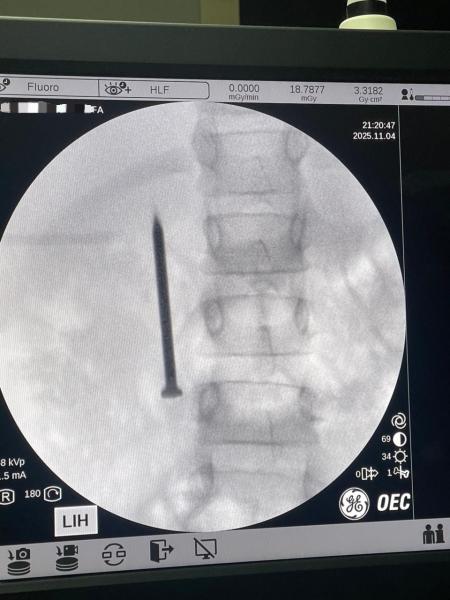

أعلن الدكتور أحمد القاصد، رئيس جامعة المنوفية، عن نجاح فريق طبي متخصص بوحدة مناظير الجهاز الهضمي بمعهد الكبد القومي في إنقاذ حياة طفلة تبلغ من العمر 7 سنوات، بعد ابتلاعها مسمارًا معدنيًا حادًا يبلغ طوله 4 سنتيمترات.

وأوضح رئيس الجامعة أن الفريق الطبي تمكن من استخراج المسمار الذي وصل إلى الجزء الأول من الأمعاء الدقيقة (الصائم) عبر إجراء منظار طارئ لم يستغرق سوى 20 دقيقة، متجنبًا بذلك خطر الثقب أو النزيف أو الانسداد المعوي الوشيك، حيث غادرت الطفلة المستشفى بصحة جيدة بعد التدخل الطبي السريع.

من جانبه، أكد الدكتور أحمد صيرة، أستاذ طب كبد الأطفال ورئيس وحدة مناظير الأطفال وقائد الفريق الطبي، أن استخدام المنظار كان الخيار الأمثل لتجنب إجراء عملية جراحية مفتوحة أكثر إرهاقًا للطفلة، مشددًا على أهمية التدخل السريع في مثل هذه الحالات لتفادي مضاعفات محتملة مثل الثقب أو النزيف أو الانسداد المعوي.